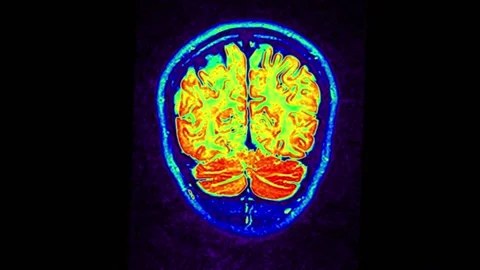

"As physicians, we have never been more optimistic that millions of people take steps today to lower their risk for Alzheimer’s."

Read more“I believe we have reached a watershed moment in recognizing the factors that lead to the decline of brain health."

"A prevention-centric model—move, eat smart, sleep well, connect, train the brain, and manage cardiometabolic risk..."